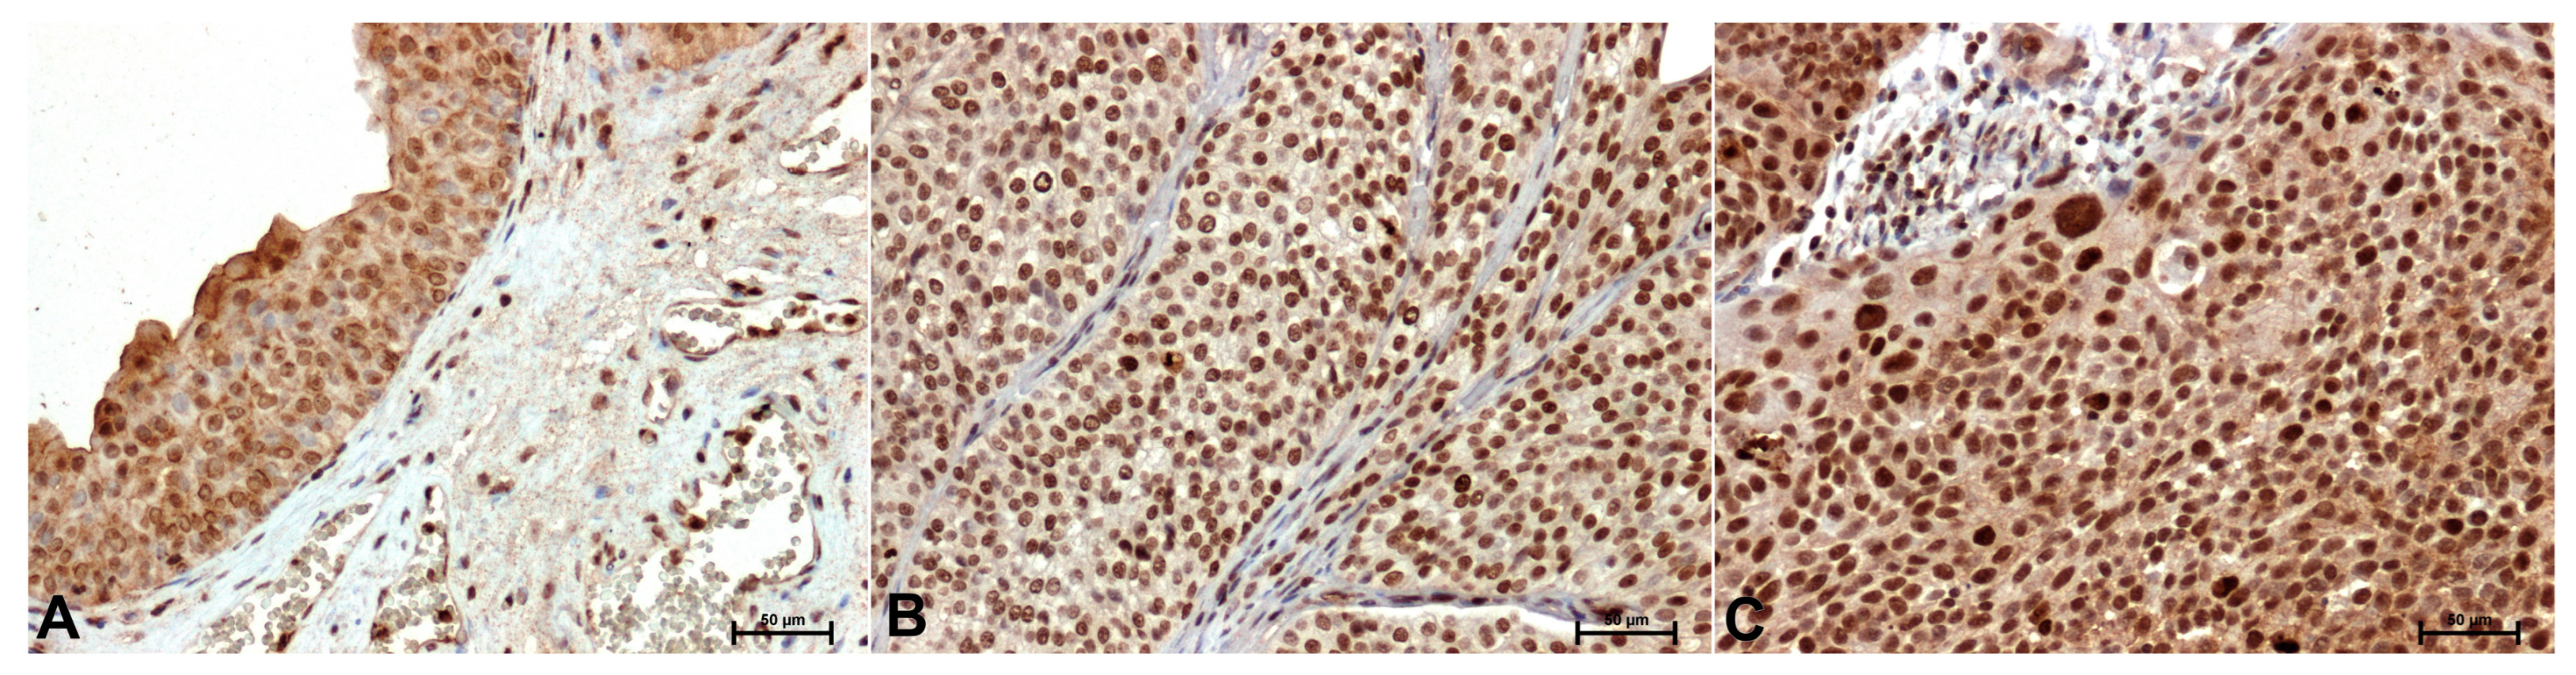

| CacyBP/SIP | 71.14 ± 1.37 | 108.87 ± 1.59* | 145.76 ± 1.21* |

| ERK1/2 | 120.04 ± 1.93 | 91.28 ± 1.16* | 121.21 ± 1.08 |

| p38 | 96.81 ± 1.14 | 143.62 ± 1.11* | 159.79 ± 1.22* |